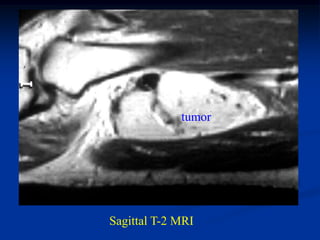

Case #309

Coronal T-1 MRI

45 year male with hemangiopericytoma thigh

Axial T-1 MRI

Axial proton density MRI

tumor

Axial T-2 MRI

Case #309 Coronal T-1 MRI 45 year male with hemangiopericytoma thigh

• 420.

• 421.

• 422.

tumor Axial T-2 MRI